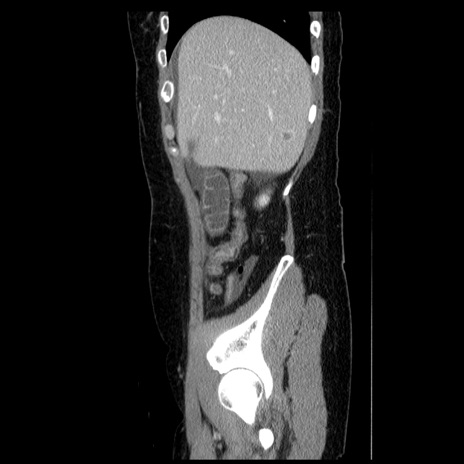

症例6(矢状断像)

冠状断像